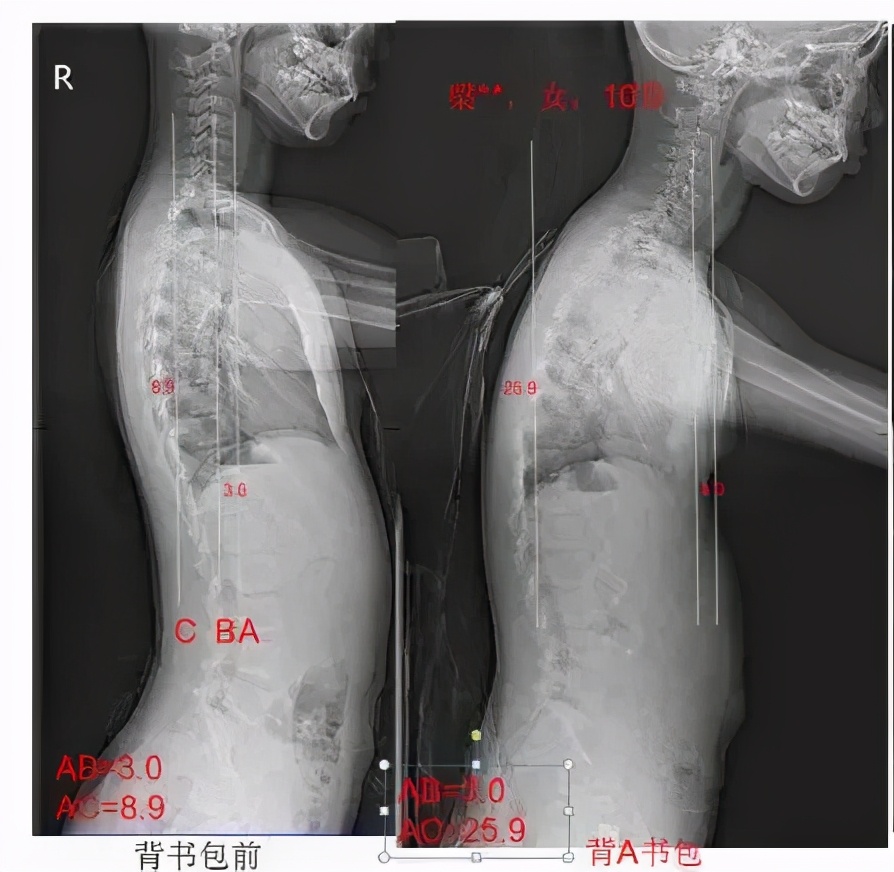

背书包前后,脊柱(尤其颈椎)生理曲度改变

这样一是会使头颈过度前探来维持身体的平衡,继而导致颈部肌肉的疲劳酸痛和颈椎应力的改变;二是容易导致驼背。青少年儿童正处于身体快速发展的阶段,脊柱正在快速发育,背包对学生脊柱形态的影响将会表现得更明显。